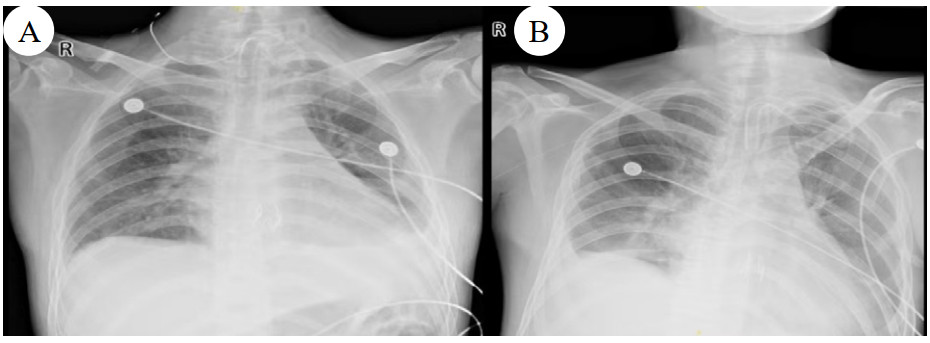

| 注:图A为B某;图B为C某 图 6 患者肺移植术后胸片 |

|

| 注:图A为B某;图B为C某 图 7 肺移植术后第2个月、5个月、8个月CT影像 |